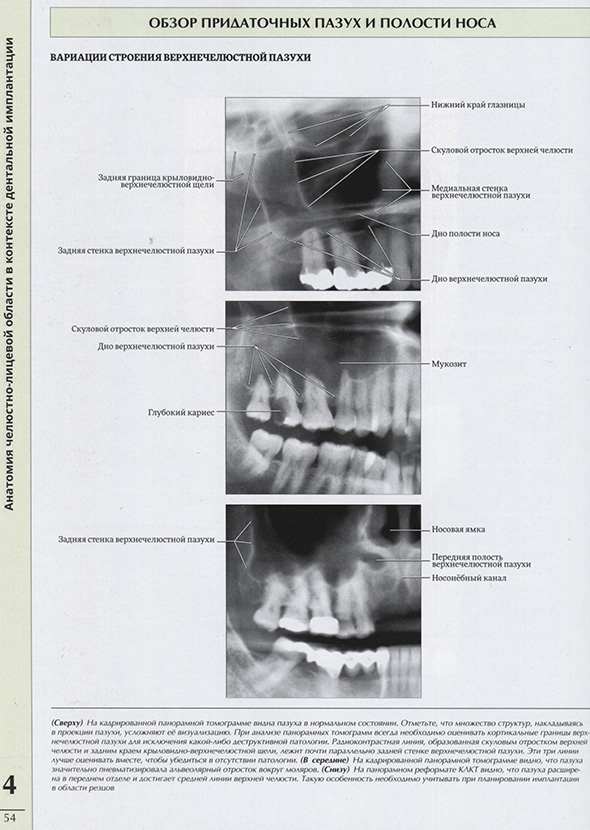

Обзор придаточных пазух и полости носа